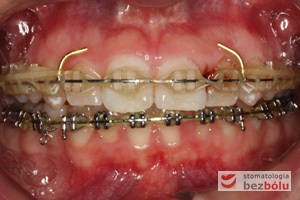

Pacjentka lat 22 zgłosiła się do naszej placówki celem podjęcia leczenia ortodontycznego. Głównym oczekiwaniem pacjentki była poprawa estetyki uśmiechu oraz brak ekstrakcji zębów na drodze do jej uzyskania. Ze względu na liczne stłoczenia zębów w górnym i dolnym łuku, dość duży materiał zębowy w porównaniu z bazą kostną, a także zgryz przewieszony boczny prawostronny po dokładnej analizie cefalometrycznej oraz analizie modeli diagnostycznych zastosowano leczenie bezekstrakcyjne z wykorzystaniem strippingu jako alternatywy dla usuwania zębów, mającego na celu uzyskanie miejsca w łuku na uszeregowanie zębów. Po fazie aktywnego leczenia trwającego 18 miesięcy zastosowano leczenie retencyjne w postaci szyny retencyjnej w łuku górnym oraz retainera stałego w łuku zębowym dolnym klejonego od kła do kła.